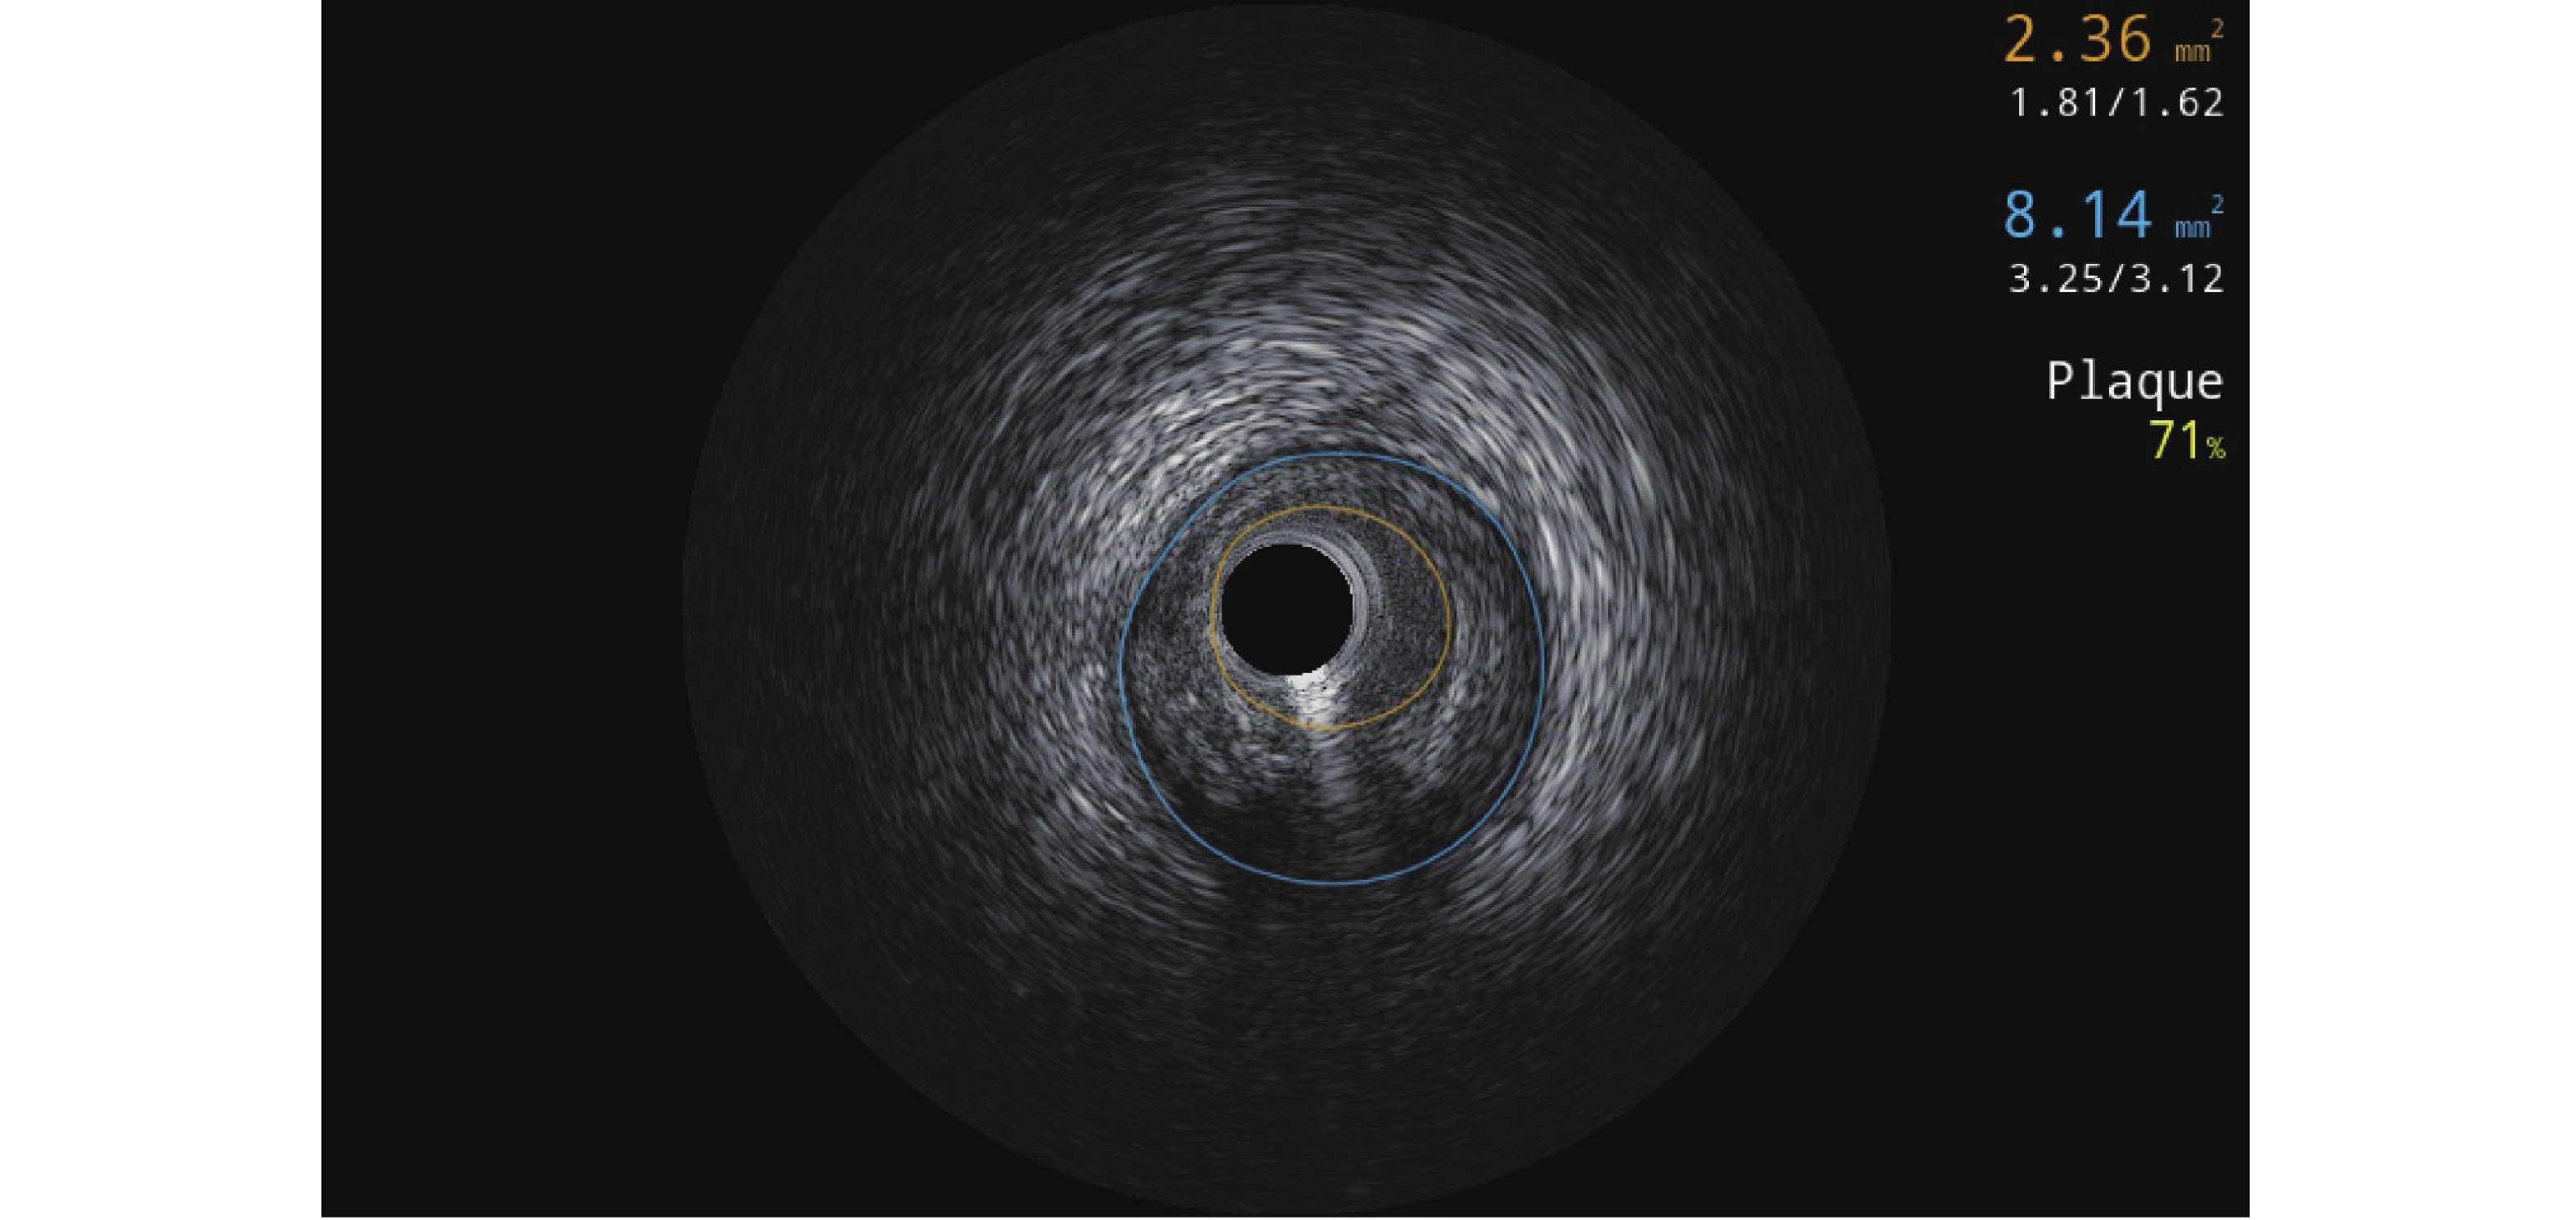

典型心绞痛合并中重度钙化病变的冠心病患者应用可视Stent Boost支架精显指导介入治疗的效果

陈红梅, 赵郑波, 胡云, 李俊

摘要(122) HTML(87) PDF (29)

摘要:

目的   探讨可视支架影像增强显影技术(Stent Boost)精显指导典型心绞痛合并中重度钙化病变的冠心病患者介入治疗的效果。  方法   前瞻性选取2022年1月至2024年1月180例典型心绞痛合并中重度钙化病变的冠心病患者作为研究对象,按照随机数字表法分为对照组(n = 90)与实验组(n = 90),并根据实际病情分为中度钙化亚组(n = 30)、重度钙化亚组(n = 30)、特殊人群亚组(n = 30)。对照组采用标准支架植入治疗方案,实验组采用可视Stent Boost精显指导+标准支架植入治疗方案,支架均选择药物洗脱支架。比较两组术中操作便利性及手术效果,以及手术前后心功能指标[左心室射血分数(left ventricular ejection fraction,LVEF)、左心室收缩末期容积(left ventricular end-systolic volume,LVESV)、左心室舒张末期容积(left ventricular end-diastolic volume,LVEDV)]、并发症。并随访12个月,观察对比两组靶病变血运重建、主要不良心血管事件(major adverse cardiovascular events,MACE)事件。  结果   实验组术中即刻支架可视性优良率、支架膨胀率、最小支架管腔直径、最大支架边缘直径、最小支架管腔面积(minimal stent area,MSA)、偏心指数、LVEF均高于对照组,且后扩张率、手术时间、对比剂用量、LVESV、LVEDV均低于对照组(P < 0.05);实验组术后即刻心肌梗死溶栓治疗(thrombolysis in myocardial infarction,TIMI)分级 3级血流比例高于对照组,并发症发生率、MACE发生率低于对照组(P < 0.05);但两组中度钙化亚组、重度钙化亚组、特殊人群亚组术后即刻TIMI 3级血流比例单独比较,差异均无统计学意义(P > 0.05);两组中度钙化亚组、重度钙化亚组患者并发症发生率、MACE发生率比较,差异无统计学意义(P > 0.05);实验组中特殊人群亚组并发症发生率、MACE发生率低于对照组的特殊人群亚组(P < 0.05)。  结论   对于典型心绞痛合并中重度钙化病变的冠心病患者,Stent Boost指导PCI可优化治疗效果,改善术后心功能,降低并发症及MACE发生率,尤其在重度钙化合并分叉病变的患者中价值显著。